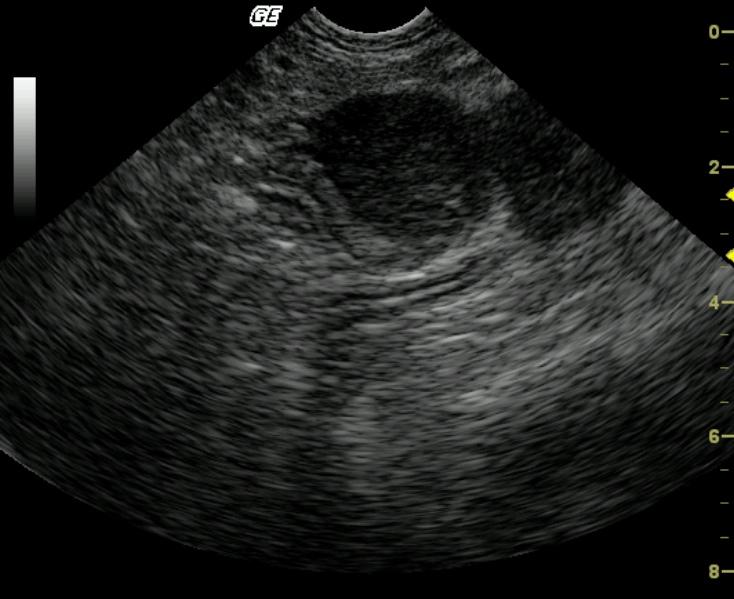

A hypoechoic, essentially bi-lobed small bowel wall mass is asymmetrically arising from a segment of distal small bowel. The serosal borders are undulating, however, the serosal layer appears to be intact.

Bolbedmasswithundulatingserosasmallbowelmass